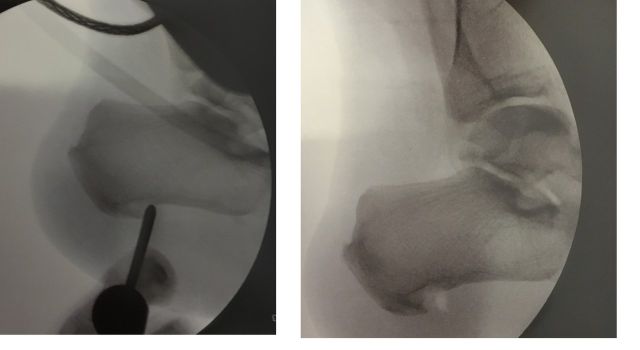

Kann konservativ keine Verbesserung erreicht werden, stellt die Sehnenkerbung der Plantaraponeurose, am besten unter arthroskopischer Kontrolle, eine effektive Therapievariante dar.

Diese wird normalerweise kombiniert mit einer arthroskopisch kontrollierten Knochenspornabtragung am Fersenbein, um eine neuerliche Druckproblematik verhindern zu können.

Eine genaue Abklärung der Ursachen ist jedoch vorher unablässig, um mögliche Fehlstellungen des Fersenbeines zu erkennen und gegebenenfalls mitkorrigieren zu können.